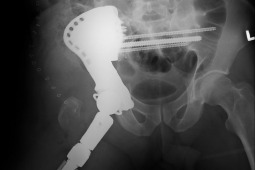

Trudność operacji wynikała z rozległości zmian nowotworowych, a jej innowacyjność i wyjątkowość polegała na wykonaniu rekonstrukcji funkcji połowy miednicy i stawu biodrowego z użyciem bardzo dużego implantu wykonanego specjalnie dla pacjenta na podstawie badań obrazowych.

Po konsultacjach medycznych lekarze z Kliniki Ortopedii Ogólnej, Onkologicznej i Traumatologii postanowili uratować kończynę. Kierujący zespołem onkologicznym Jacek Markuszewski podjął współpracę z amerykańską firmą specjalizującą się produkcji implantów w technologii, w rezultacie czego na podstawie badań obrazowych wspólnie najpierw zaprojektowano a następnie wykonano specjalną endoprotezę będącą dokładnym odwzorowaniem kształtu i wielkości miednicy pacjenta. Implant zastępuje połowę miednicy i staw biodrowy umożliwiając ponownie chodzenie.

Innowacyjność projektu endoprotezy polegała na wiernym odtworzeniu anatomii miednicy i dokładnej lokalizacji stawu biodrowego względem mięśni działających na staw. Nowatorski sposób połączenia implantu z kością umożliwił trwałe „biologiczne” połączenie z kością i zachowaniu funkcji układu nerwowego.

Trudność operacji polegała na „doczepieniu” endoprotezy do pozostałej drugiej połowy miednicy pacjenta. Wybrano innowacyjne mocowanie długimi śrubami poprzez kość krzyżową, która zawiera struktury układu nerwowego. Dzięki zastosowaniu specjalnych przymiarów, wykonanych na podstawie tomografii komputerowej nie naruszono żadnych struktur układu neurologicznego, co jest zwykle jest typowym powikłaniem w tego typu zabiegach.